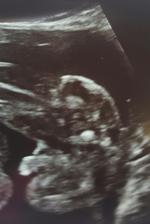

Gratuluji, je to veliký zázrak!!🙂 Z ničeho je malý tvoříček!! 🙂 už se těšíme na druhé,l ale ješte si poškáme, termín máme 01.01.2017